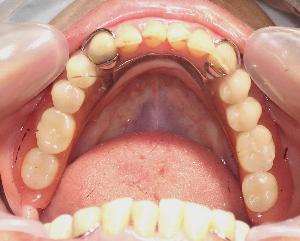

部分入れ歯は何本かの歯が連なって失われてしまった場合に作成します。部分的な入れ歯です。床(しょう)という土台の上に、バネと人工歯で支えとなる歯に取り付ける仕組みです。形はお口と歯の状態で決まります。 |